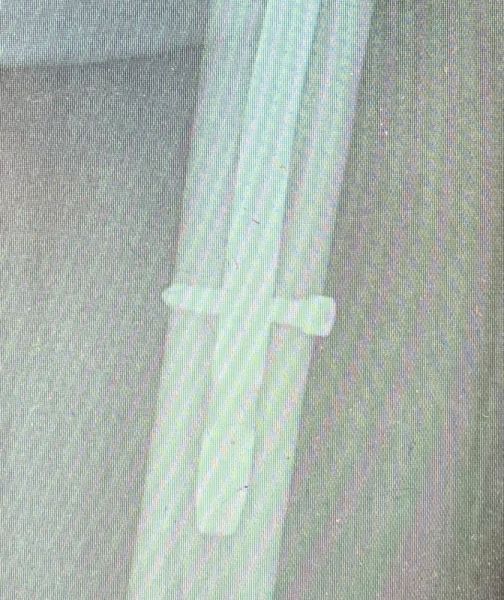

3. Intra-articular fracture of the left distal tibia associated with lateral malleolar fracture in a 33-year-old female.

Treatment: 1st step, external fixation. 2nd step, after 14 days removal external fixation and at the same time open reduction internal fixation (ORIF)

I. Before surgery II. 1st step, the external fixator III. 2nd step, removal the external fixator and at the same time (ORIF)